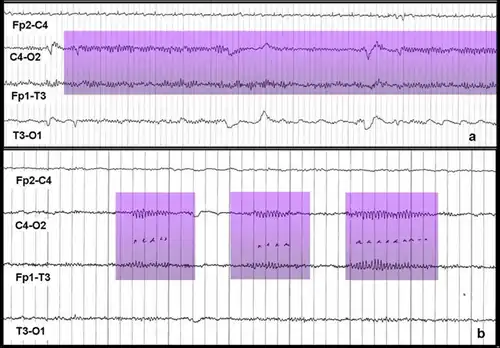

Мю-ритм (μ-ритм, роландический ритм, сенсомоторный ритм, аркоидный (arceau) ритм, аркообразный (wicket) ритм, гребенчатый ритм, дугообразный ритм) — ритм головного мозга — периодические колебания биопотенциалов в сенсомоторной области коры головного мозга на частоте 8 — 13 Гц (чаще всего 9 — 11 Гц). Эти колебания могут быть зарегистрированы методами электроэнцефалографии (ЭЭГ), магнитоэнцефалографии (МЭГ), или электрокортикографии (ЭКОГ). Наиболее выражен в состоянии физического покоя. В отличие от альфа-ритма, который возникает на аналогичной частоте в задней части головы над зрительной корой также в состоянии покоя, мю-ритм локализован над моторной корой. У человека подавление мю-ритма происходит, когда он или она выполняет какое-либо движение или, после определённой тренировки, когда он или она визуализирует (представляет) выполнение движений. Это подавление называется десинхронизация (уменьшение амплитуды сигнала), потому что причиной появления ритмических паттернов на ЭЭГ является синхронная активность большого числа нейронов. Кроме того, мю-ритм подавляется когда человек наблюдает за выполнением движений другого человека. Рамачандран и его коллеги предположили, что это является признаком того, что зеркальная нейронная система участвует в подавлении мю-ритма[1][2], однако, есть и противники этой теории[3]. Мю-ритм представляет интерес для множества учёных. Например, при изучении развития нервной системы, интерес представляют подробности формирования мю-ритма в младенчестве и детстве и его роль в процессах обучения[4]. Поскольку некоторые исследователи считают, что расстройства аутистического спектра (РАС) во многом связаны с изменениями в системе зеркальных нейронов[1][5][6], и что подавление мю-ритма отражает активность зеркальных нейронов[2], многие из этих учёных заинтересованы в изучении мю-ритма у людей с расстройствами аутистического спектра. Мю-ритм широко используется при построении мозг-компьютерных интерфейсов (МКИ). С развитием МКИ систем, врачи надеются дать людям с тяжёлыми инвалидностями новые способы коммуникации, средства для манипулирования и перемещения в пространстве[7].

Интерфейсы мозг-компьютер (ИМК) — активно развивающаяся технология, которая, как полагают, однажды сможет дать бо́льшую независимость людям с инвалидностями. Предполагается, что эти технологии смогут помогать людям почти полностью или даже полностью парализованным, например с такими заболеваниями как тетраплегия (квадриплегия) или боковым амиотрофическим склерозом. ИМК могут помочь таким больным в общении или даже позволят контролировать движение инвалидных кресел и нейропротезов[7][17]. Одним из типов МКИ является интерфейс, использующий событийно-связанную десинхронизацию мю-ритма для управления компьютером[7]. Этот метод мониторинга активности мозга основан на том факте, что когда группа нейронов находится в состоянии покоя они, как правило, возбуждаются синхронно. Если оператор МКИ мысленно представит движение («событие»), произойдёт десинхронизация (связанная с «событием»). Нейроны, которые до этого возбуждались синхронно, приобретут свои индивидуальные, не похожие друг на друга паттерны возбуждения. Это приведёт к уменьшению амплитуды регистрируемого сигнала, которое может быть зафиксировано и проанализировано при помощи компьютера. Операторы подобных МКИ тренируются визуализировать движения ногами, руками и/или языком. Эти части тела имеют удалённые друг от друга проекционные зоны коры головного мозга и поэтому их легче всего отличить друг от друга на основе записей электроэнцефалограммы (ЭЭГ) или электрокортикограммы (ЭКоГ) с электродов размещённых над моторной корой[7][18]. Событийно-связанная десинхронизация может быть использована вместе с другими методами мониторинга электрической активности мозга, позволяя создавать гибридные ИМК, которые часто оказываются более эффективными, чем ИМК использующие только один метод мониторинга[7][18].

В отличие от α-ритма, μ-ритм активируется во время психической нагрузки и психического напряжения. Выполнение любых движений независимо от их структуры, силовой, временной, пространственных характеристик всегда сопровождается блокированием μ-ритма. Ритм также блокируется мысленным представлением движения, состоянием готовности к движению или тактильной стимуляцией. Мало реагирует на воздействия других раздражений, например, световых и звуковых[2]. Выражен у слепых, компенсирующих потерю зрения развитием тактильного и двигательного исследования среды, у которых он встречается в три раза чаще по сравнению со зрячими. Также μ-ритм выражен у спортсменов (в пять раз чаще, чем у лиц, не занимающихся спортом)[21].